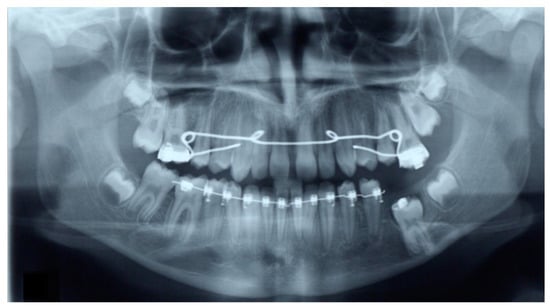

2. Case Presentation